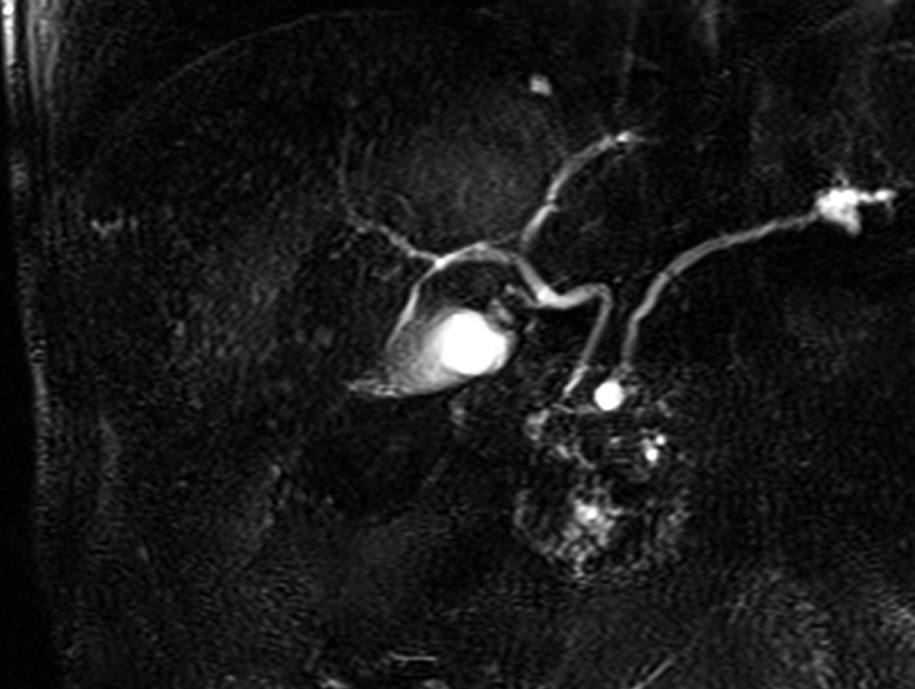

In T2-weighted MRI–cholangiography sequences, the liver presents a “starry sky” appearance due to the presence of multiple small hyperintense lesions; however, the communication with the bile duct are usually not recognized [7] (Fig. 4).

Fig. 4. MRI image with T2 MRI–cholangiography sequence: multiple small hyperintense lesions; the liver with a “starry sky” appearance.